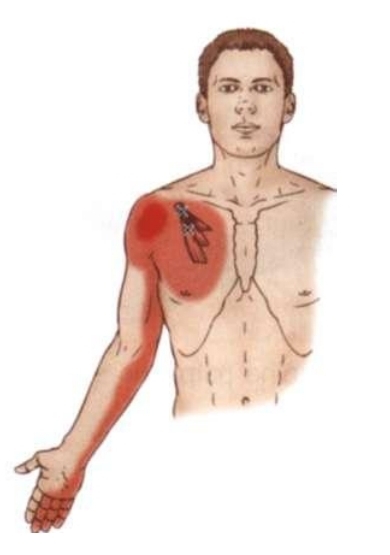

트리거포인트 / Trigger Point

<소흉근/작은가슴근 트리거포인트 원인>

1. 급성 혹은 만성적 과사용

2. 근육이 짧아진 자세를 장시간 지속 (ex. 만성적 둥근어깨 자세, 팔이 접혀 몸통을 가로지른 상태로 바로누운자세로 수면

3. 지팡이 혹은 목발 사용

4. 심근경색증(myocardial infarction)

5. 과도한 호흡

6. 무거운 가방때문에 근육의 압박

7. 대흉근/큰가슴근 혹은 목갈비근의 트리거포인트

<트리거포인트에 의한 유발>

1. 소흉근증후근(pectoralis minor syndrome) - 신경학적 혹은 혈관성 증상이 상지에서 유발될 수 있다.

2. 둥근어깨 자세(rounded shoulder posture)

3. 어깨의 당김(retraction)의 제한

4. 익상견갑(winging of scapula)